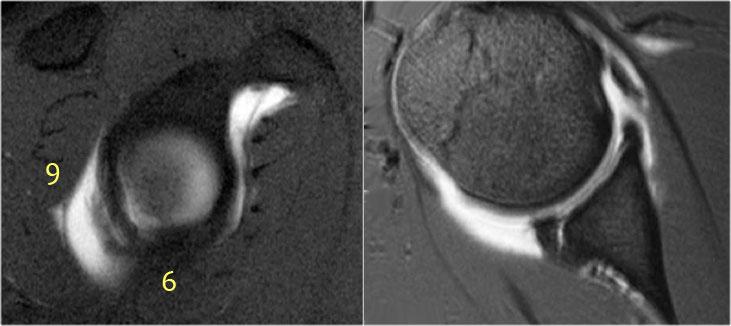

Tổn thương Perthes là avulsion sụn viền-dây chằng tương tự Bankart, nhưng với màng xương bị bóc tách về phía trong mà vẫn còn nguyên vẹn.

Trên hình ảnh khớp vai ở tư thế trung gian, sụn viền bị rách có thể được giữ ở vị trí giải phẫu bình thường bởi màng xương bả vai còn nguyên vẹn, từ đó ngăn thuốc tương phản từ thấm vào đường rách.

Điều này có nghĩa là MRI khớp cản từ ở tư thế trung gian có thể không phát hiện được đường rách sụn viền.

Tuy nhiên, ở tư thế ABER, dây chằng ổ chảo-cánh tay dưới bó trước bị căng tạo lực kéo lên sụn viền trước-dưới, giúp tăng khả năng phát hiện đường rách.

Mũi tên chỉ vào màng xương còn nguyên vẹn.

Các hình ảnh ở tư thế ABER cho thấy sụn viền trước bị bong tách.

Hình bên phải được xoay 90° ngược chiều kim đồng hồ.

Đôi khi điều này giúp hiểu rõ hơn về giải phẫu.